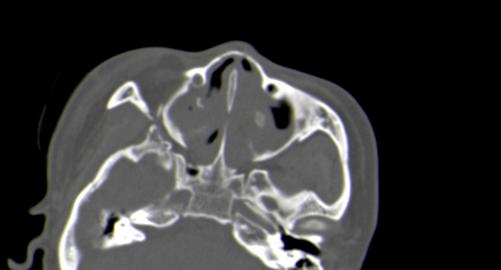

以下是引用皎皎白驹在2006-11-29 8:48:00的发言:[br]影像表现:双侧筛窦和上颌窦、鼻腔内均密度增高,右侧视神经增粗、弯曲,左筛窦顶部筛板及右侧纸板近视神经孔区可见骨折线。[br]结合临床表现考虑:右侧筛窦纸板近视神经孔区骨折致右侧视神经损伤。最好做个眼眶冠状扫描,更明确右侧视神经管是否狭窄。

以下是引用w_jianhua在2006-11-29 10:07:00的发言:[br]影像表现:双侧筛窦和上颌窦、鼻腔内均密度增高,右侧视神经增粗、弯曲,左筛窦顶部筛板及右侧纸板近视神经孔区可见骨折线。[br]结合临床表现考虑:右侧筛窦纸板近视神经孔区骨折致右侧视神经损伤。最好做个眼眶冠状扫描,更明确右侧视神经管是否狭窄。 [br] [br]支持[br]

以下是引用守望可可西里在2006-11-29 9:46:00的发言:[br][quote]以下是引用皎皎白驹在2006-11-29 8:48:00的发言:[br]影像表现:双侧筛窦和上颌窦、鼻腔内均密度增高,右侧视神经增粗、弯曲,左筛窦顶部筛板及右侧纸板近视神经孔区可见骨折线。[br]结合临床表现考虑:右侧筛窦纸板近视神经孔区骨折致右侧视神经损伤。最好做个眼眶冠状扫描,更明确右侧视神经管是否狭窄。